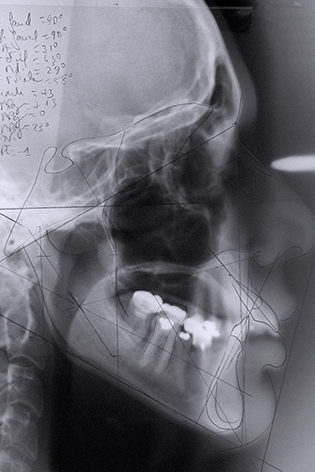

L’orthodontie permet de corriger la position des dents et des mâchoires. En fonction de l’âge et de l’endroit où il y a un déséquilibre dentaire, appelé malocclusion, le traitement peut aussi permettre d’agrandir la mâchoire. On peut par exemple agrandir la mâchoire du haut ou élargir celle du bas.